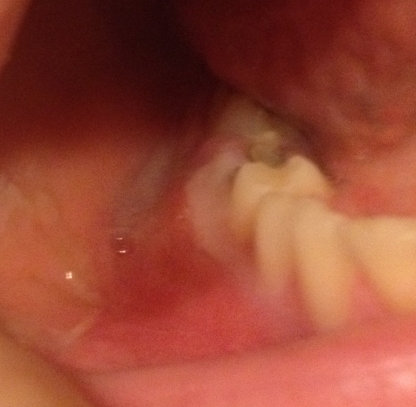

Мне 15 лет. Сегодня начал болеть двадцать восьмой зуб. Болит при надавливании или просто при закрывании рта очень сильно и существует чувство "выросшего" зуба. На нем имеются две маленькие дырочки, еле заметные. Опухла десна возле этого зуба, она также болит при надавливании.